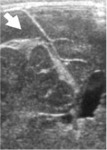

визуализации дефекта паренхимы печени на момент осмотра (рис.1 а.).

Рисунок 1. Ребенок С., осмотр в день

поступления.

| а - сканирование в правом подреберье через 4 часа после травмы. В проекции правой

доли печени определяется значительных размеров зона гетерогенного повышения эхогенности.

Небольшое количество жидкостного компонента подкапсульно. |

б - через 9 часов после травмы при сканировании в В-режиме из косо-поперечного

доступа в эпигастрии определяется значительных размеров дефект паренхимы правой

доли печени (анэхогенный участок неправильно-овальной формы). |

в - 9 часов после травмы, тот же доступ, сканирование в режиме

энергетического допплера. В проекции дефекта паренхимы печени определяется бессосудистая

зона. В неповрежденных участках паренхимы сосудистый рисунок сохранен. |